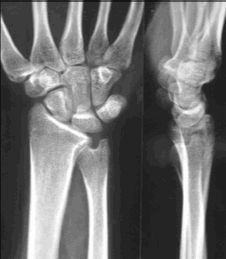

Congrès - Compte rendu Le scaphoïde : de la fracture à l'arthrose. Nice 30 septembre et 1er octobre 2004 , Alain Thebaud Clinique Jeanne D'Arc, 44000 Nantes, France , Christian Dumontier Hôpital Saint-Antoine, Paris, France N°146 - Août 2005 ● 17 min de lecture

Mise au point Quelques nouveautés dans la chirurgie du poignet , Christian Dumontier Hôpital Saint-Antoine, Paris, France , Ph. Bellemère Institut Montpelliérain de la Main et du Membre Supérieur, Clinique Clémentville, 25 rue Clémentville, 34070 Montpellier, France N°93 - Avril 2000 ● 11 min de lecture

Mise au point Examen clinique des traumatismes ligamentaires du poignet , Christian Dumontier Hôpital Saint-Antoine, Paris, France N°49 - Décembre 1995 ● 32 min de lecture